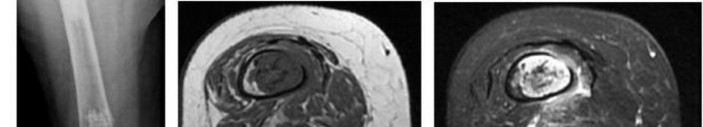

A 15-year-old male presents with deep knee pain awakening him at night. Radiographs show a permeative destructive lesion in the distal femoral metaphysis with a 'sunburst' periosteal reaction and Codman's triangle.

Biopsy confirms high-grade conventional osteosarcoma. What is the most critical prognostic factor for long-term overall survival in this patient?

Explanation

For localized high-grade osteosarcoma, the most important prognostic indicator is the histologic response to neoadjuvant chemotherapy. This is evaluated during the definitive resection. A 'good response' is typically defined as greater than 90% or 99% tumor necrosis. Patients who achieve this level of necrosis have a significantly improved disease-free and overall survival rate compared to 'poor responders' who have extensive viable tumor cells remaining.